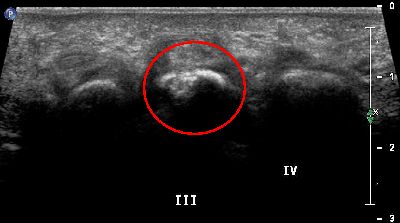

Pannicolo fibrotico intrarticolare

(caso del paziente G.V.)